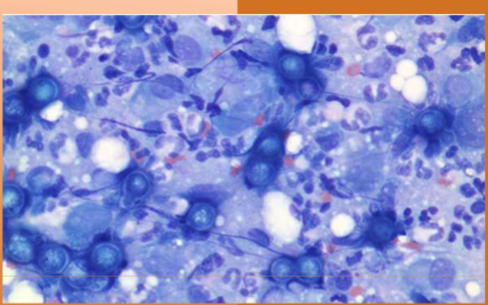

Histoplasma capsulatum

Histoplasmosis

what does Histoplasma capsulatum infect

dogs, cats, and humans

what does Histoplasma capsulatum cause

Fever, lethargy, weight loss, diarrhea, loss of appetite, coughing and labored or rapid breathing, eye infections, such as chorioretinitis or retinal detachment, pain or lameness in the joints